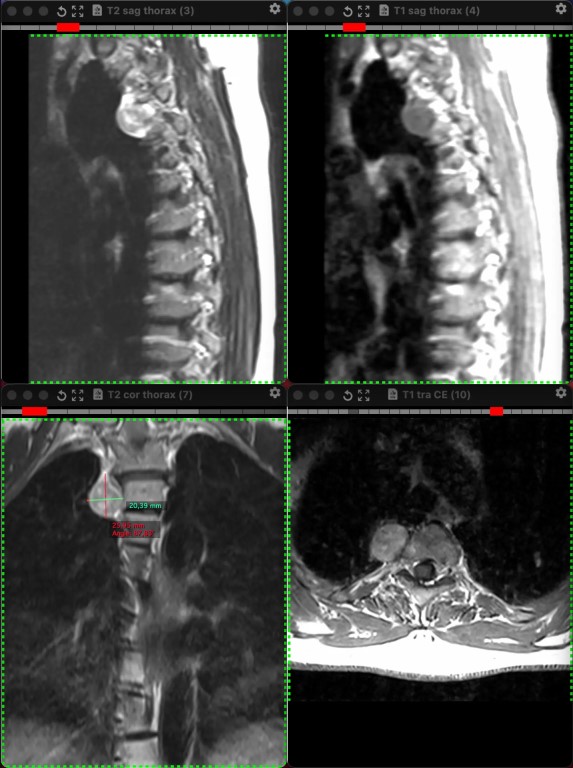

Фото И ещё одна предполагаемая шваннома заднего средостения у женщины, на сей раз 38 лет, обследованной не по её поводу. Бессимптомная, как и почти всегда.